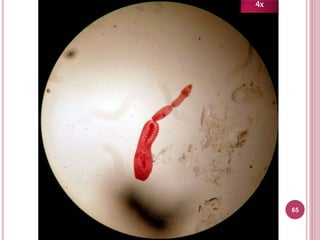

65

4x

Características

 Útero racemoso

 Poro genital posterior

Tiene útero

racemoso

(¡Parece un

racimo!)